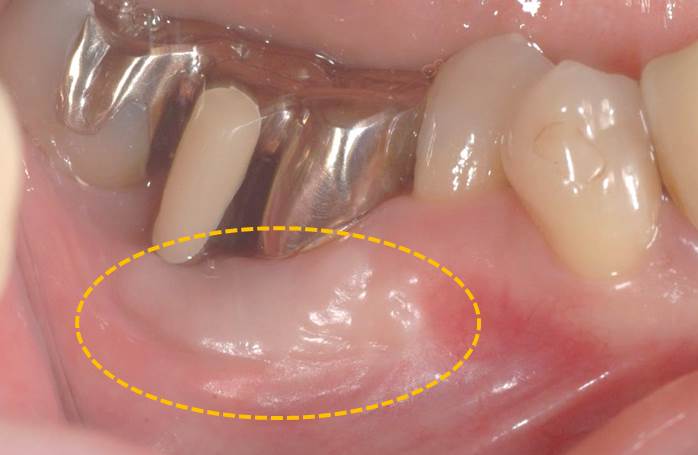

オレンジ○の部分が移植後2ヶ月になります。

動かない歯茎(歯肉)が形成され、ブラッシングが行いやすくなっただけではなく、歯と付着することで歯周組織の健康も維持されやすくなりました。